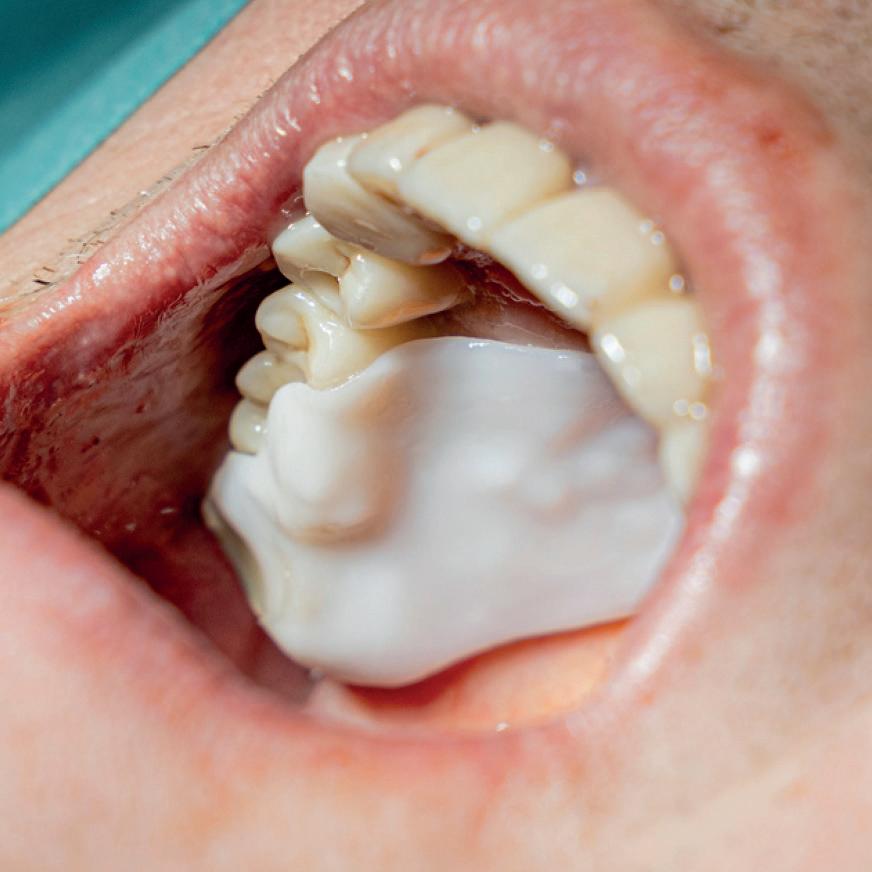

Elemental Antibacterial Wound Dressing

A Revolution in Bone Graft Protection

Minimise Complications and Improve Healing Conditions In Mucogingival and Implant Surgery

Leveraging the antibacterial and wound-healing properties of zinc ions, Elemental can be used post-operatively with or without a membrane.

Elemental activates when in contact with boiling water, and the resulting material, which sets rigid and stable, can be quickly and easily moulded and shaped according to the needs of the patient.